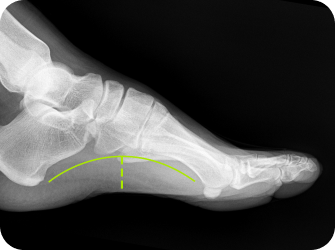

족궁 높이 측정

발 뒤꿈치 각도 검사

평발, 요족, 까치발,

발의 변형 등 족부 문제를

맞춤형 깔창으로 교정